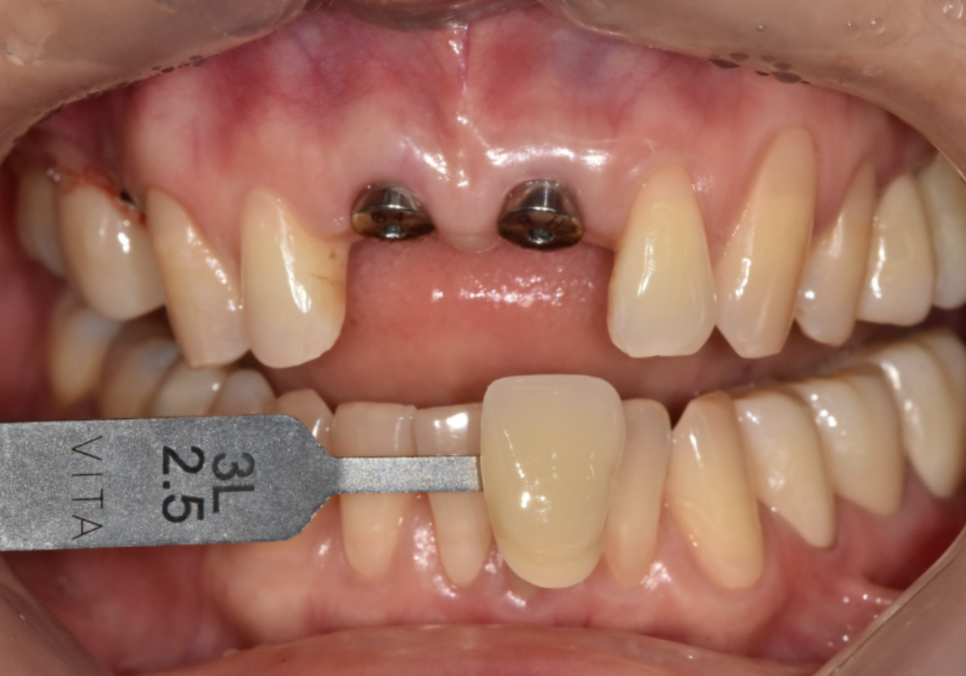

최종 보철 제작

잇몸 까매짐 원인,증상,치료 방법

4개월 후 임플란트가 뼈와 잘 유착되었는지

확인하기 위해 기계로 수치를 재어본 뒤

높은 수치가 나온 것을 확인하고

보철을 제작하기 위해 본을 뜹니다.

저희 병원은 원내 기공실이 있어서

보철 제작 과정에서 미세한 부분들을

즉시 조정하고 소통할 수 있기 때문에

외부 기공소로 보낼 때보다

색상이나 형태 재현도가 훨씬 정확합니다.

250906

특히 앞니는 자연광에서 봤을 때

주변 치아와 자연스럽게 어우러져야 하는데

사진만으로는 미세한 색 차이를

구현하기 어렵거든요.

250919

이후 최종 보철물을 제작해서 부착했고,

환자분은 잇몸 색도 자연스럽게 회복되고

냄새도 사라졌다고 하셨습니다.